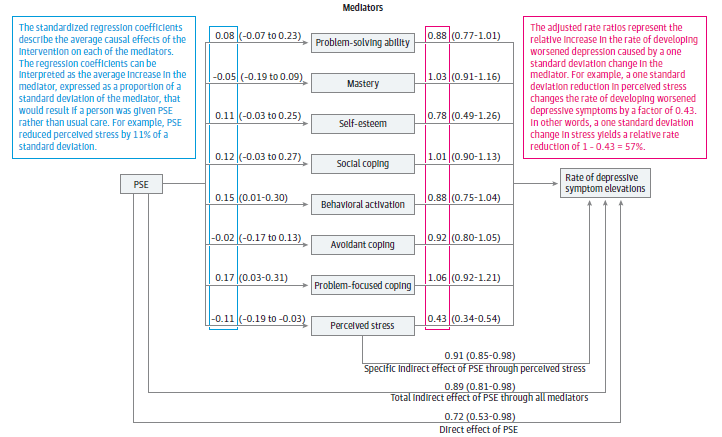

Mediation analysis estimates the proportion of an intervention's effect that is attributable to an indirect mediating variable. https://ja.ma/2IudBiJ pic.twitter.com/OcA8VDliF4